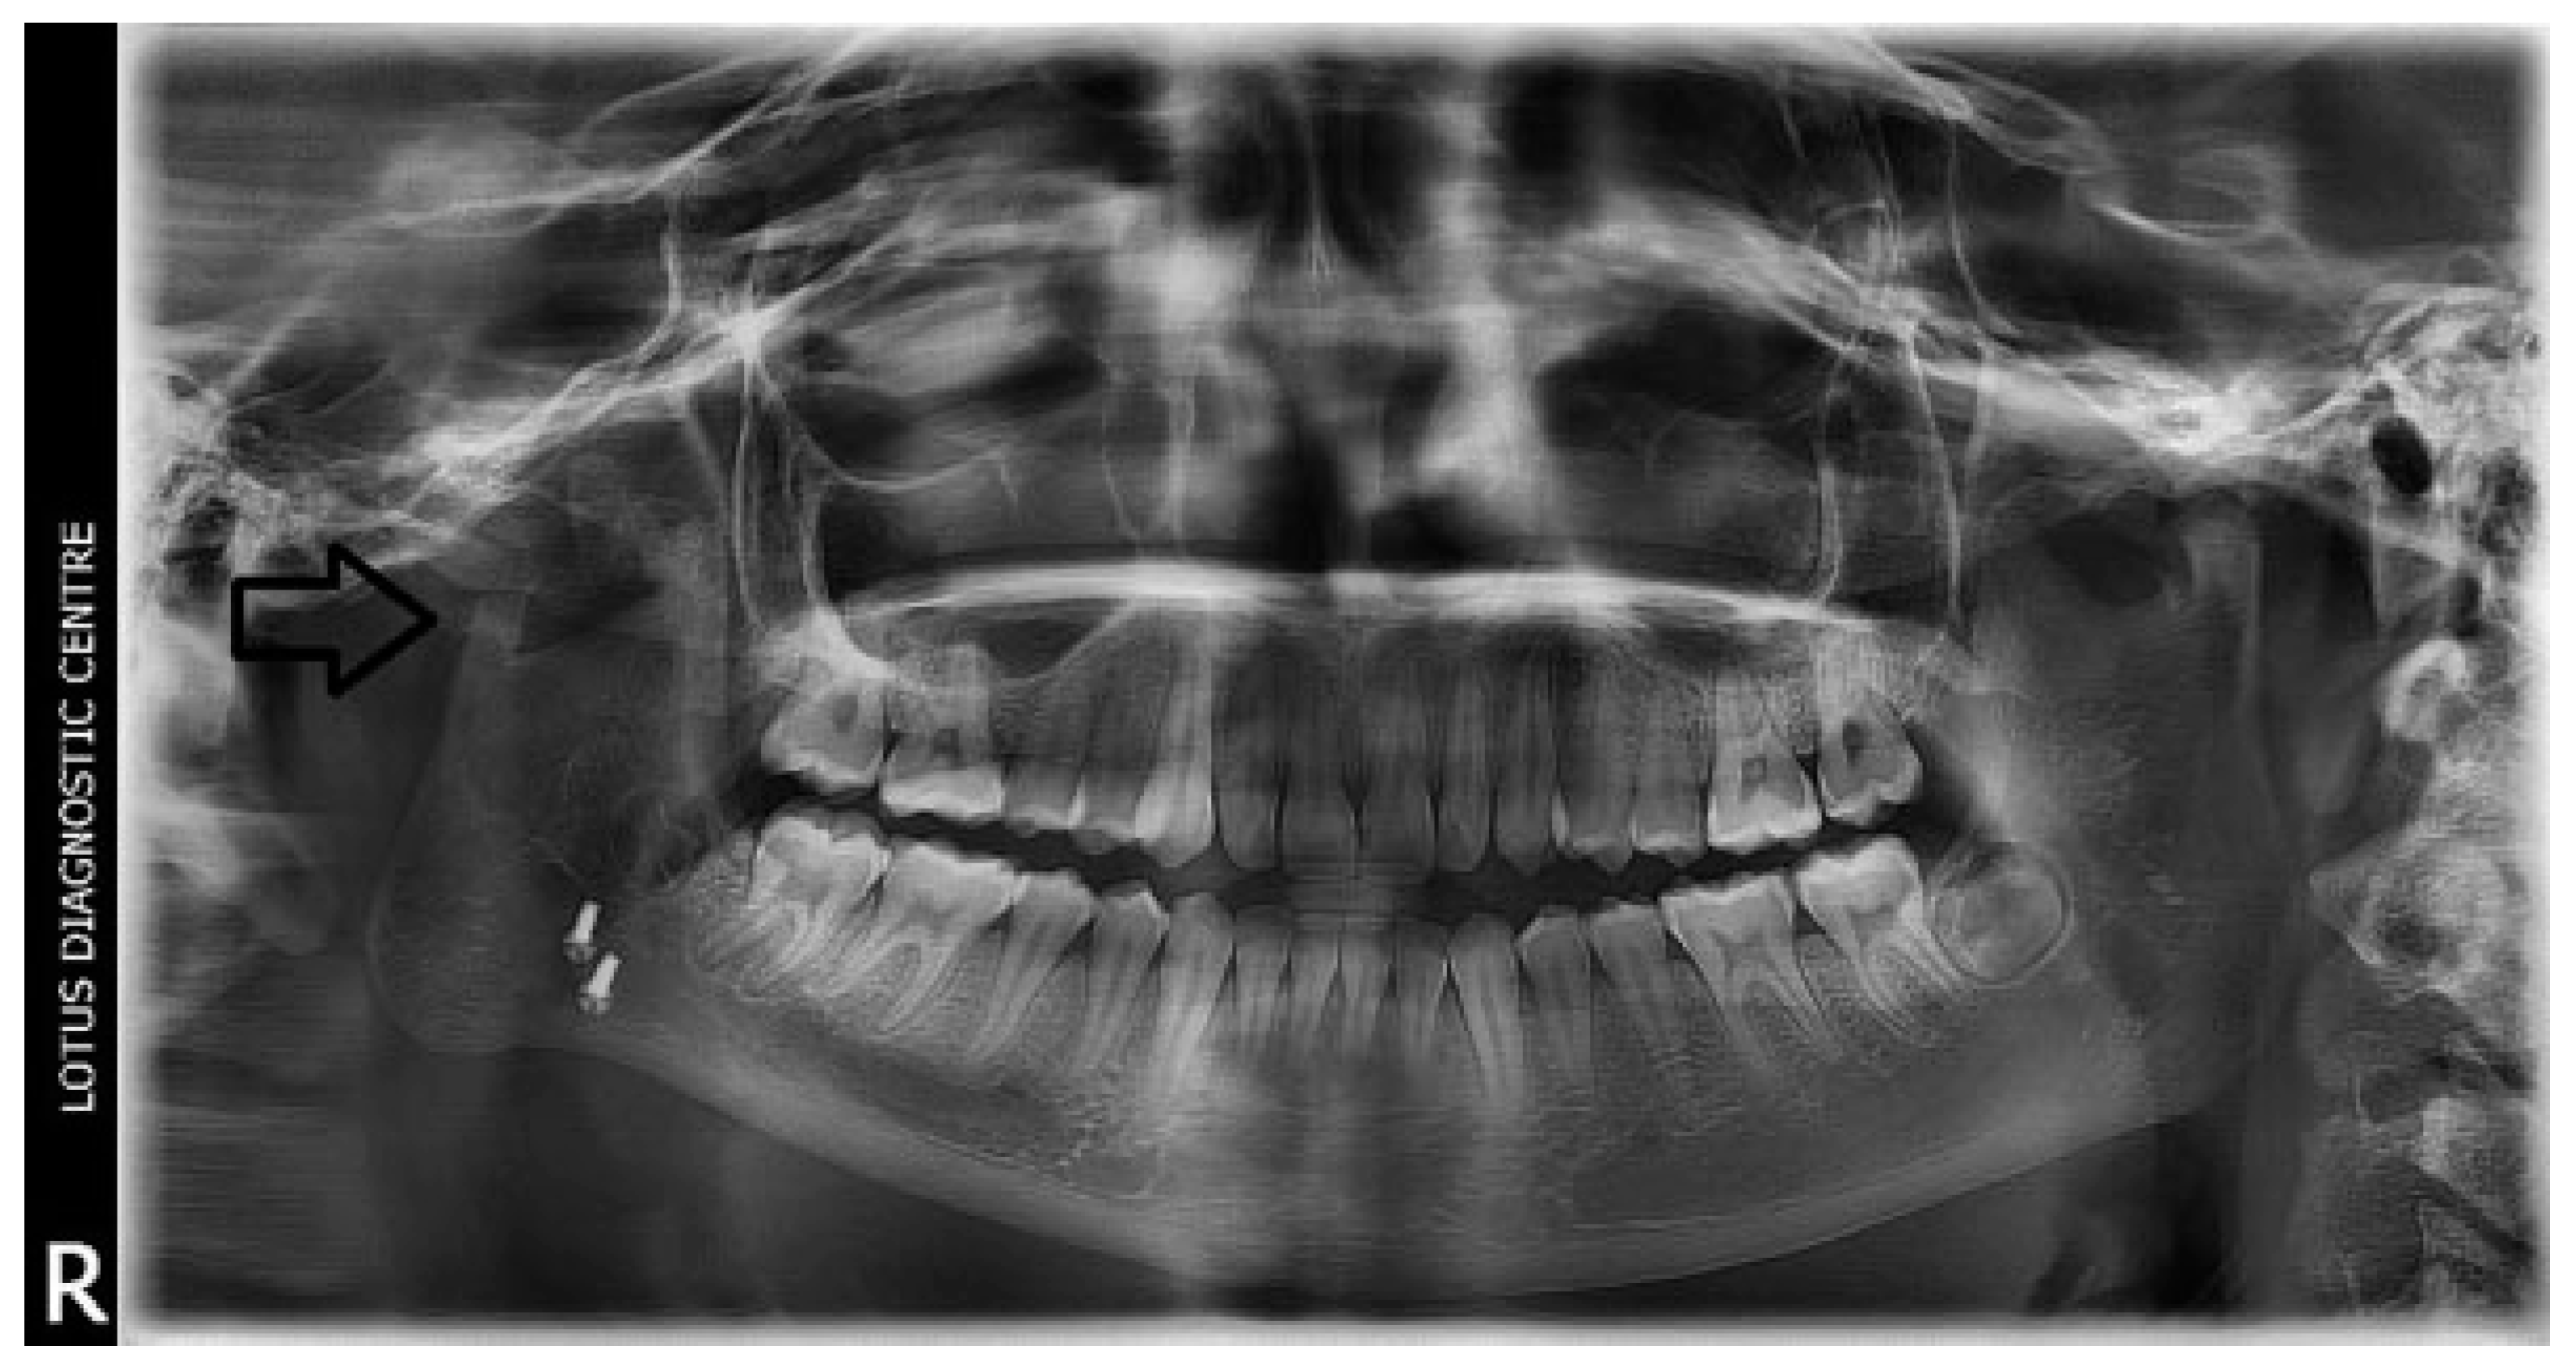

Figure 2. Postoperative OPG at 6 years of follow-up (black arrow depicting CCG graft with temporalis muscle interpositioning with respect to right temporomandibular joint).

Temporalis muscle was used in seven patients and temporalis fascia was used in two patients. In our series, using temporalis fascia as an interpositional material in the postoperative MIMO was 37 mm. Temporalis fascia has the disadvantage of being thinner, taut, and nonelastic. Long-term follow-up showed premature contact of teeth on the operated side in both the patients and the ramal height was not maintained. When the temporalis muscle was used as interpositional material, we based our flap on one of the branches of deep temporal arteries to maintain its vascularity and the flap was turned over the zygomatic arch and placed into the glenoid fossa. Temporalis muscle provided us with more bulk to obliterate the joint space and was sandwiched between the chondral end of the CCG and temporal bone. After appropriate positioning has been established, the muscle is sutured in both the anterior and posterior directions. Moreover, there is no hematoma formation and hence had better long-term stability. In patients where temporalis muscle was used, the MIMO was 41 mm and ramal height was maintained in all the cases (Figure 7 and Figure 8). The ramal height was preserved in most of our cases possibly due to unilateral ankylosis with compensation by the contralateral mandibular unit. Management of ankylosis in children can be very challenging and our aim was to correct retrognathia in bilateral cases and reduce the possibility of further asymmetry in unilateral cases. Growth center transplantation using CCGs was done in seven growing children in the 6- to 13-year age group. The uses of this biologically compatible autograft in reconstruction are benefits of growth potential and ability to remodel into a neocondyle with time. Unpredictable growth pattern of the CCG, midline shift, and donor site morbidity are some of the disadvantages of this technique. Overgrowth of the graft has been attributed to the use of a large cartilaginous cap; hence, only 1 to 2 mm cartilaginous cap must be used to avoid such complications [13,14,15]. We assessed the same using panoramic radiographs during follow-ups. The CCGs showed excellent mandibular growth along with complete integration of graft into the recipient site over the passage of time in all seven cases. The CCG was harvested from the sixth rib (contralateral side) using submammary incision and was secured using three 2-mm titanium screws at the recipient site. Due to the close proximity of the chondral cartilage to the base of skull, we routinely interposed temporalis muscle in these patients. The muscle pedicle acted as an artificial disc as well as a barrier between the base of skull and chondral cartilage (Figure 9). Early and vigorous mobilization is important to prevent postoperative adhesions and reankylosis [16]. The postoperative MIMO in seven patients was 41.5 mm. Asymmetry in the form of deviation of chin was found in one patient during long-term follow-up, where CCG overgrowth led to the deviation of the chin to the contralateral side.

The unique ability of the CCG to remodel into neocondyle could be well appreciated on the digital OPG and CT scan of the patient. The length and width of the neocondyle was very much comparable to the length of the condyle on the unaffected side at 6 years follow-up. Thus, the neocondyle formed using the costochondral cartilage was identical to the unaffected mandibular condyle both structurally and functionally. Poor socioeconomic conditions and lack of awareness coupled with poor primary health care facilities lead many of these unfortunate patients to live with this debilitating condition well into adulthood. Five such adult patients with age ranging from 17 to 36 years reported to us for treatment of TMJ ankylosis. In all these patients, ankylotic bony mass extends beyond the boundaries of the joint capsule. Alloplastic reconstruction after the release of ankylosis was our method of treatment, although high cost of condylar prosthesis led us to use 2.4 mm condylar head reconstruction plate along with temporalis muscle interpositioning in these patients. Interpositional grafts may fail to restore the ramal height in bilaterally ankylosed adult patients, so alloplastic condylar reconstruction may become the preferred choice. Advantages of alloplastic TMJ reconstruction are that the physical therapy can begin immediately, there is no need for a secondary donor site, surgery time is decreased, and alloplasts can be constructed in such a way as to mimic the normal anatomic contours of the structures they are to replace [17,18]. Wolford and Karras have suggested autologous fat transplantation as a useful adjunct to prosthetic TMJ reconstruction, as it minimizes the occurrence of excessive joint fibrosis, heterotopic calcification, and improves the range of motion [19]. However, they have categorically stated in their discussion that heterotopic bone formation is seen in multiple operated joints and joints with previously failed alloplastic implants. Another method to combat heterotopic bone formation is the use of 10 Gy of irradiation in five fractionated daily doses in the immediate postoperative period [20]. In our series, none of the patients reported with heterotopic bone formation possibly because they had undergone a single surgical procedure for managing TMJ ankylosis. The risk of fossa perforation could have been taken care by interpositioning of temporalis muscle in all these patients.